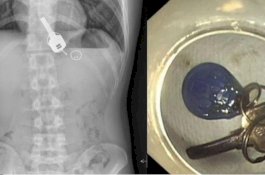

Pria Ini Cari Kunci Rumahnya yang Hilang, Tidak Sadar Ternyata Sudah Tertelan